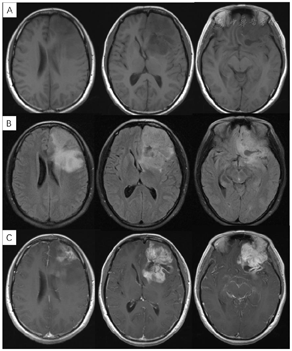

入院完善术前检查后于2017年6月7日行左额叶肿瘤切除术,术中见左侧额部约4cm×5cm大小占位,与上矢状窦、大脑镰相邻,颅底硬膜受侵犯,肿瘤质地软,呈鱼肉样外观,血供丰富,与周围脑组织分界不清。术后病理示:(左额叶)胶质母细胞瘤(WHO Ⅳ级)伴局部坏死,IDH突变型(图3)。免疫组化染色示肿瘤细胞:GFAP(部分+),S-100(+),Vimentin(+),Olig2(+),Syn(部分+),NF(灶状+),IDH(+),P53(+),ATRX(-),D2-40(-),NeuN(-),EMA(-),Ki67(热点区域Li: 15%)。分子病理结果显示:IDH1 R132H突变,TP53 R273C突变,ATRX野生型,TERT野生型,1p/19q无共缺失,MGMT启动子甲基化阳性(66%)。鉴于患者年龄相对年青,20年前有原位(额叶)脑肿瘤伽马刀治疗病史,IDH1基因突变,考虑诊断为继发性胶质母细胞瘤,IDH突变型。

术后3周患者就诊于头颈肿瘤放化疗科,专科查体:左眼睑下垂,神清,言语清晰,伸舌居中,双侧瞳孔等大等圆,对光反射存在,四肢感觉活动可,肌力肌张力正常。2017年7月MR(图4)示左额叶术后改变伴出血,病灶内侧部分考虑肿瘤残留可能。为了更好地评估术后残留病变范围和制定放疗计划,患者行11C-MET PET/CT检查(图5A-D),结果示左侧脑室前角旁-左侧基底节区团块状稍高密度影,蛋氨酸代谢异常增高,考虑肿瘤残留。参照2016 ESTRO-ACROP指南[1],继发性胶质母细胞瘤放疗GTV靶区需包含术腔、T1增强上的强化区域及T2 FLAIR上的高信号区域,术后PET/CT显像所示的氨基酸代谢活跃病灶被包含在GTV之内(图5E)。患者于2017年7月始行左额叶病灶放疗(PTV 60Gy/30F,同步口服替莫唑胺化疗75mg/m2,qd)。结束后复查PET/CT(图5F-I)示病变范围明显缩小,代谢程度较前减低,左额叶少许病变存活,遂对残留病灶局部放疗加量(GTV如图5J,6Gy/3F)。放疗过程顺利,期间出现Ⅲ°白细胞减低,予以升白细胞治疗后好转出院。后于2017年10月起口服替莫唑胺辅助化疗(150~200mg/m2,d1-d5,q28d),期间规律复查。

2018年3月、6月MR复查发现病灶范围逐渐增大(图6),提示不除外复发可能。患者除了轻微头痛之外并无明显不适,临床考虑假性进展,予安维汀100mg治疗后症状好转。2018年8月复查11C-MET PET/MR显像未见明显代谢增高病灶,证实为假性进展(图7)。2018年11月复查未见明显肿瘤复发,2019年3月2日MRI复查(图8)再次提示病变增大,考虑肿瘤进展。2019年3月行PD-1单抗(拓益)治疗,治疗过程中患者出现行走不稳,1月后患者不慎跌倒,外院就诊行颅脑CT未见明显出血。期间发现患者肝功能异常,给予护肝治疗后好转。2019年5月复查PET/MR(图9)提示左侧额叶前下部、左侧海马区及左侧颞叶前部蛋氨酸代谢较前次增高,其中左侧海马及左额叶直回ASL灌注相对增高,考虑复发可能,免疫治疗后存活。遂停用免疫治疗,根据患者全基因组测序结果选择靶向药物安罗替尼治疗(主要针对VEGFR、PDGFR、FGFR、c-KIT多个靶点),2019年12月复查PET/MR(图10)提示病变活性受抑。电话随访得知患者因武汉疫情影响无法按期治疗和复查,后合并肺部感染,于2020年8月去世。